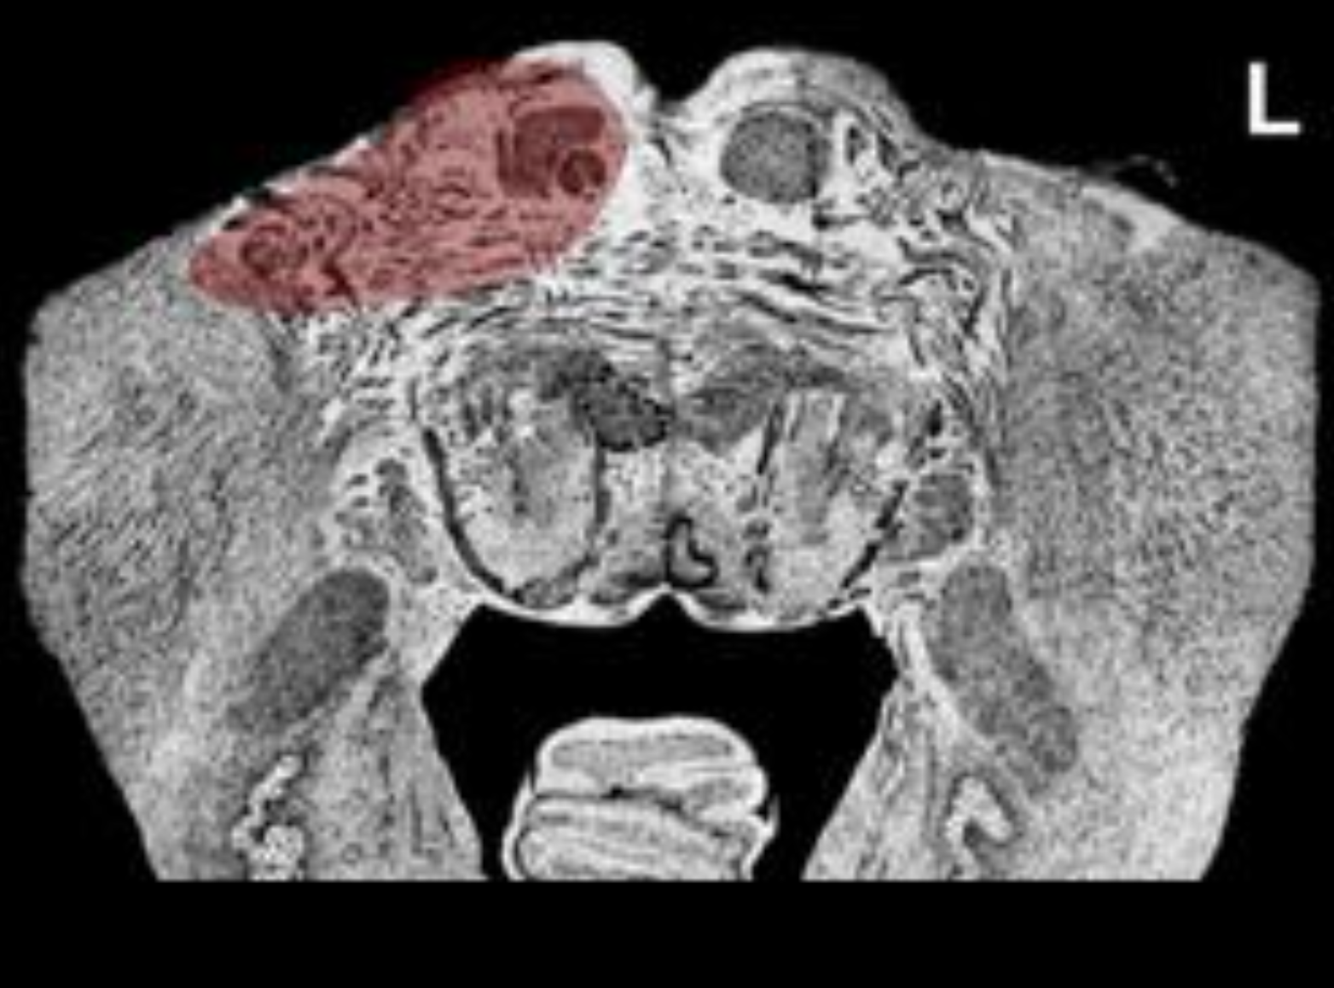

What is the name/location/results of the condition caused by a lesion in the shaded area?

Pons at the facial colliculus

Alternating Abducent Hemiplegia, Pons at facial colliculus

What condition will be caused by a lesion in the shaded area?

Syndrome of Fovill “Al6+ML”

Syndrome of Foville

includes the signs of alternating abducens hemiplegia plus additional signs due to the dorsal extension of the lesion.

Destruction of the medial lemniscus results in contralateral loss of proprioception, 2-point tactile discrimination, and vibratory sensations from the body.

Destruction of the medial longitudinal fasciculus results in internuclear ophthalmoplegia. [see syndrome of the MLF in vestibular system].

Facial nerve may also be involved.

Destruction of the crossed corticobulbar fibers results in denervation of the ipsilateral nucleus ambiguus+ hypoglossal nucleus